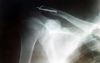

Klíčni kost

Byl jsem moc divokéj na mtb a odnesla to klíční kost

Stane se, klička to je hned. Nevidím nikde žádný úlomky, nesmrdí to komplikacemi, tak ať seš zas brzy fit!

Děkuji zítra mě čeká operace tak doufám že brzo budu šlapat zas